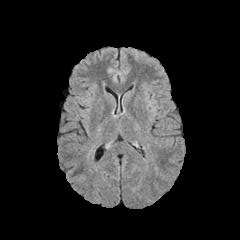

We use two popular medical imaging datasets primarily used for the evaluation of lesion segmentation: the Multimodal Brain Tumor Segmentation Challenge 2018 dataset (BratS18) [21, 2] and the Liver Tumor Segmentation Challenge dataset (LiTS).

BratS18.

The BratS18 dataset provides 210 high grade glioma (HGG) and 75 lower grade glioma (LGG) MRI with binary masks for the tumor (or lack of tumor). Each 3D MRI contains 155 slices of size 240×240240240240\times 240. Not every slice contains a tumor, and therefore healthy MRI are provided by this data as well. We use the FLAIR modality image for all the experiments because the entire tumor is represented well by this modality.However, we also show more experimental results on other modalities, where the ANT-GAN provides impressive visual quality. A more detailed medical description of the data can be found on the challenge website.111https://www.med.upenn.edu/sbia/brats2018.html

Aside from the difference in imaging tissue and modality of these two data sets, the tumor regions on the CT images are of different shape and size, as can be seen in Figure 4. Also, many CT scans are acquired in a way that introduces greater noise-like artifacts than MRI. For each dataset, 80%percent8080\% of randomly selected data are used for training and the resting 20%percent2020\% for testing.